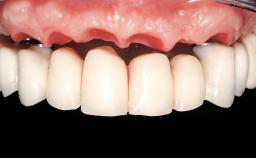

A 35-year-old Caucasian female presenting with advanced periodontal disease involving both the maxillary and the mandibular dentition was referred for evaluation. The patient, a non-smoker in good general health, requested treatment for recurrent periodontal abscesses, tooth mobility, and discomfort during chewing, as well as restoration of her missing teeth with a fixed prosthesis to improve mastication and esthetics. All residual maxillary teeth exhibited plaque deposits, deep pockets, bleeding on probing, and class III mobility and were evaluated as hopeless. All residual mandibular teeth except tooth 37 could be maintained after periodontal therapy.

Conventional Loading of Eight Implants in the Maxilla and Final Restoration with a Full-Arch Gold-Ceramic FDP